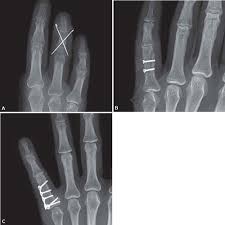

For fractures of the middle phalanx if conservative treatment is not sufficient then percutaneous pinning or open reduction using K-wires is used. Treatment principles for proximal and middle phalangeal fractures. Phalangeal fractures of the hand are a common injury that presents to the emergency department and clinic.

Middle phalangeal fractures proximal to the FDS insertion have an apex dorsal angulation whereas fractures distal to the FDS insertion have an apex volar angulation as shown in the figure. Undisplaced or minimally displaced fractures of the diaphysis of the middle phalanx can be treated non-operatively.

Remodeling occurs in the flexion-extension plane but radial or ulnar deviation and rotation must be corrected. Variably lose some function and are divided into two groups those. However if it takes more than 30 degrees of flexion to reduce the fragment operative treatment is indicated. The management of phalangeal fractures is based on the initial severity of the injury and depends on the success of closed reduction techniques. A Pilon Fracture at the base of the middle phalanx is another common break that involves the joint its usually accompanied by cartilage injury and frequently needs surgery to restore the joint surface. For the vast majority of phalanx fractures an acceptable reduction is manageable with non-operative treatment. Your fracture will be treated with splinting taping or casting or a combination of all three.